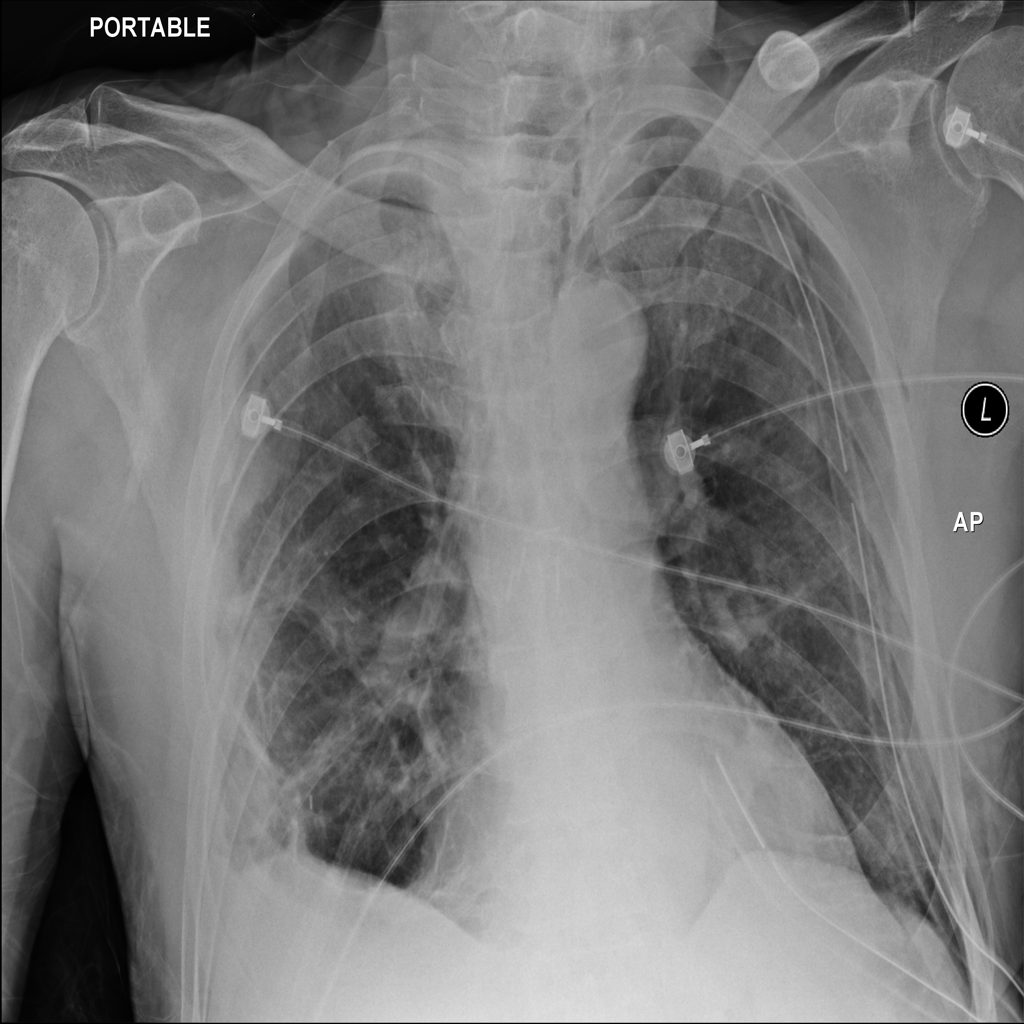

PAT-0B33 · IMG-014Pneumothorax

PAT-0B33 · IMG-014

AP